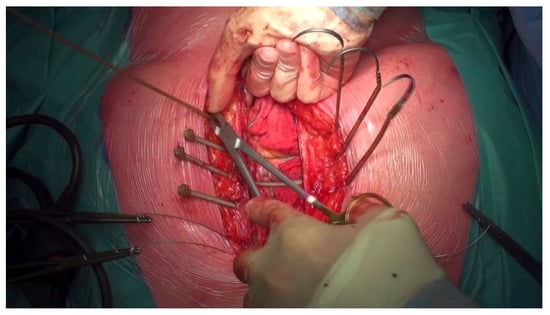

2.3. Surgical Approach